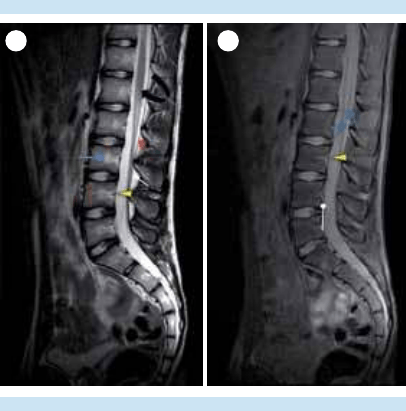

4. Evaluación de las articulaciones face-

tarias, láminas, pedículos, procesos

transversos y espinosos; del canal central

y los recesos laterales.

5. Evaluación de las 3 “c”: cordón espinal,

cono medular y cauda equina.